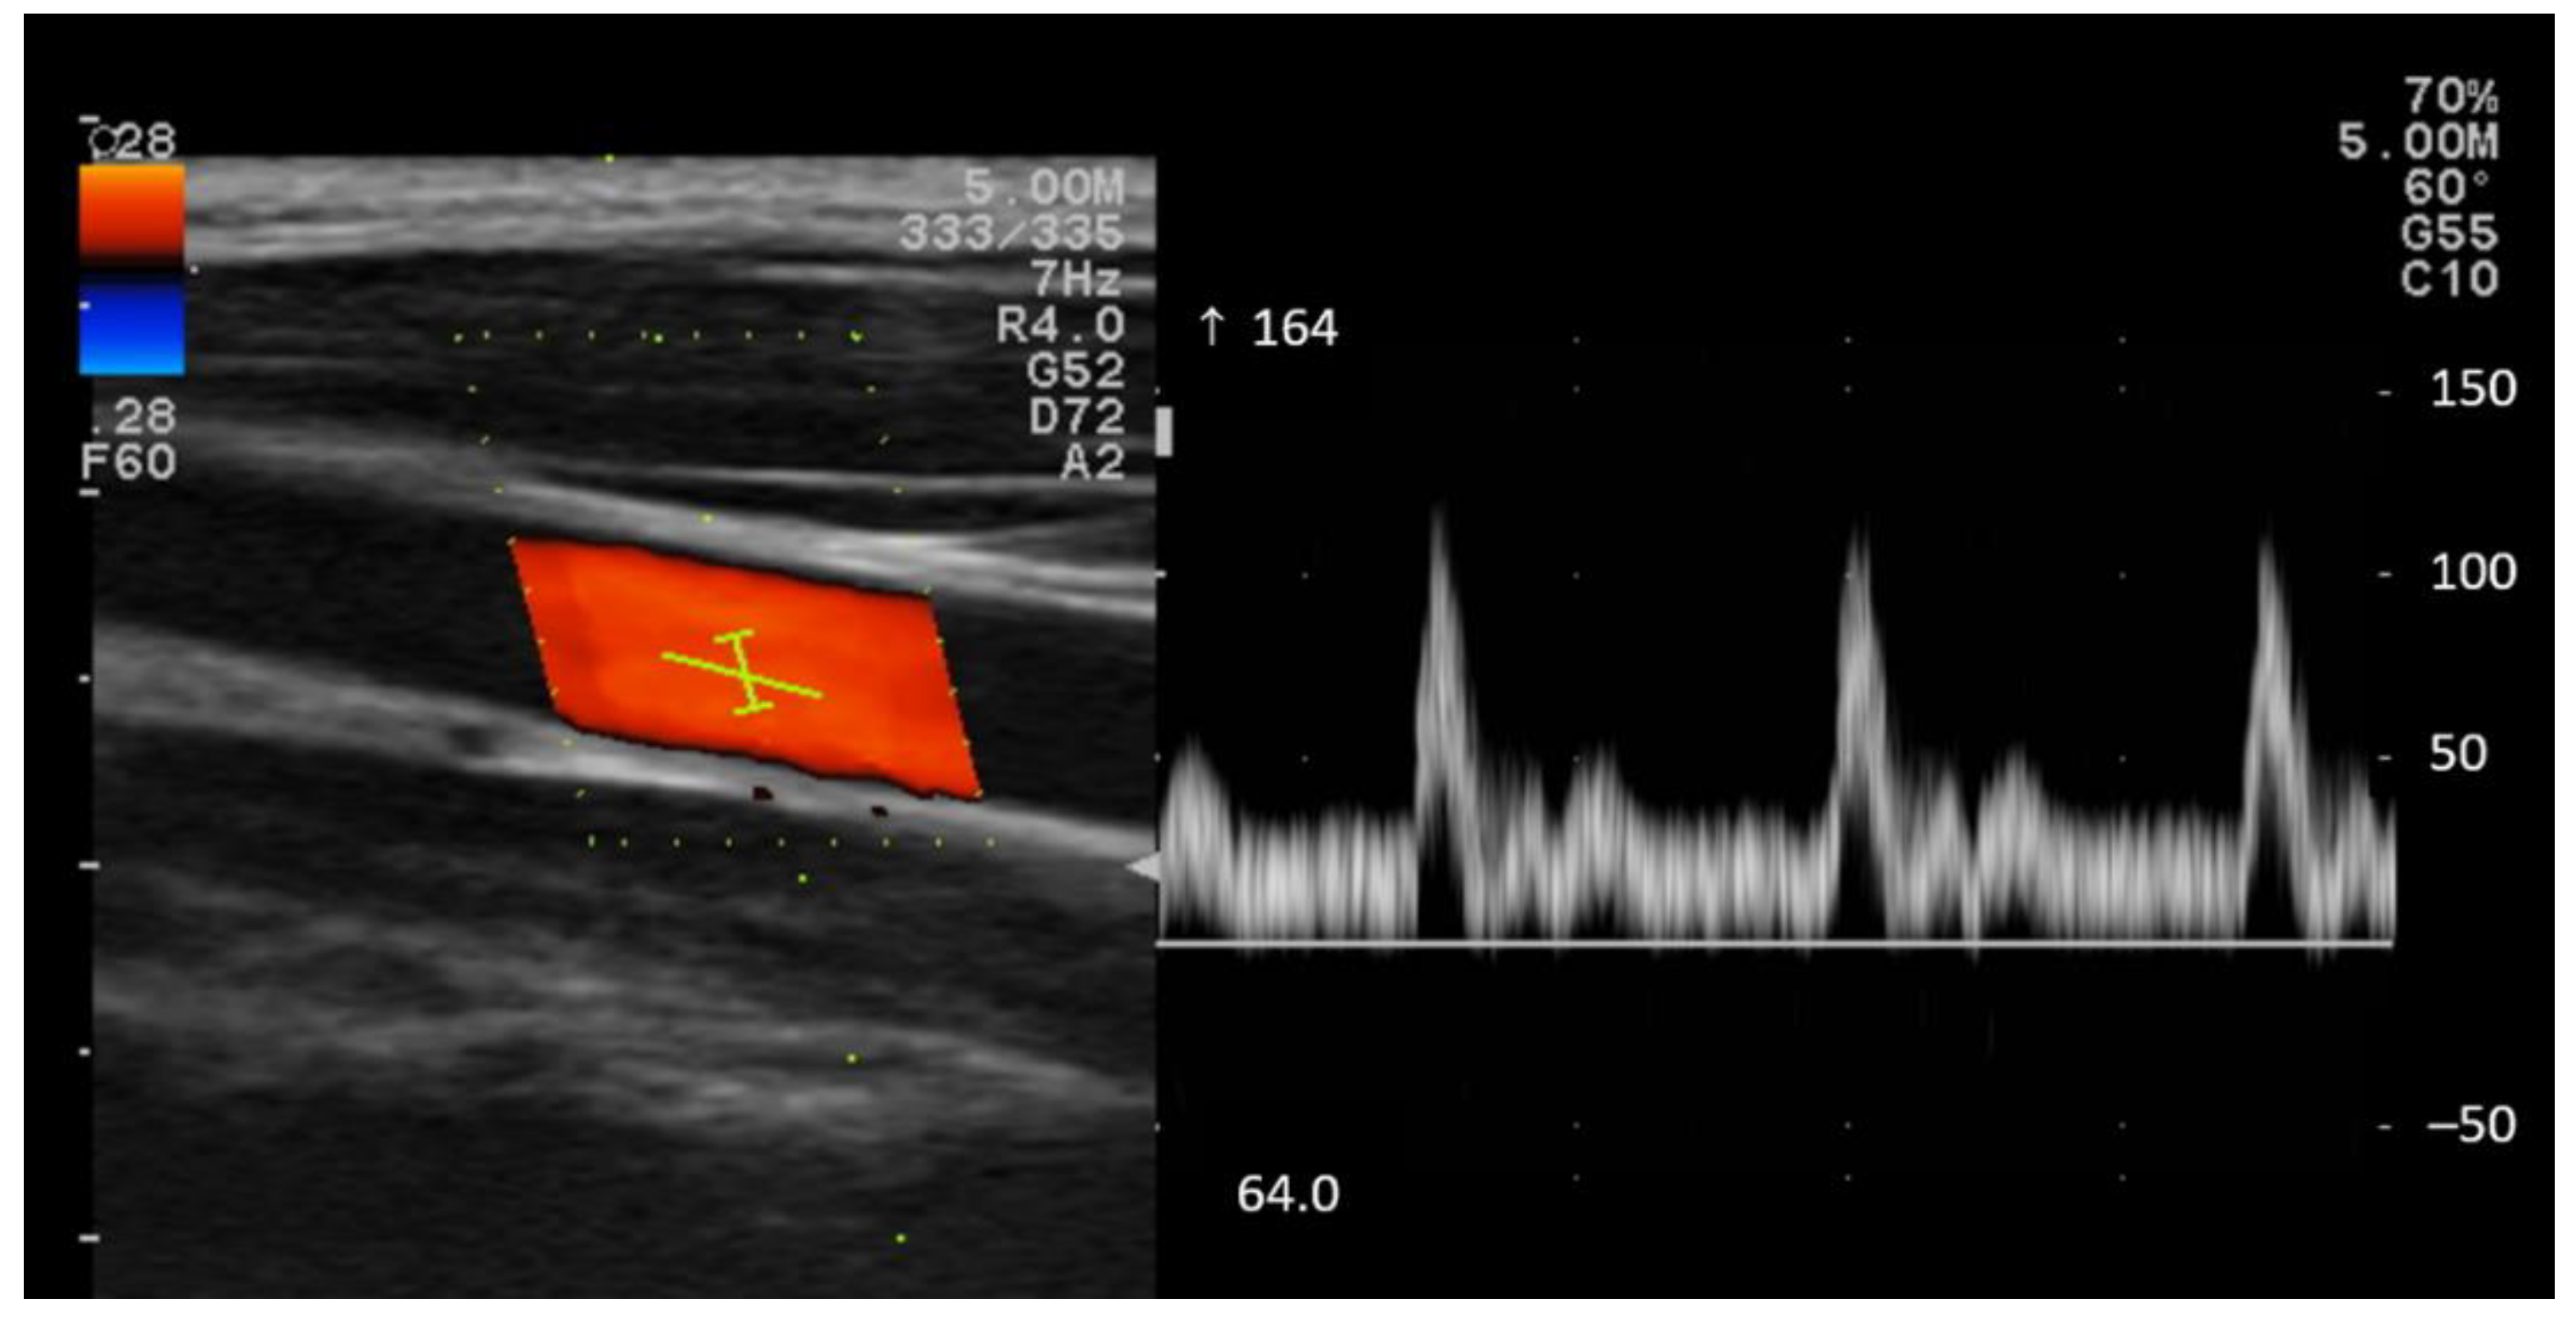

The systolic peak velocity (PSV) and end-diastolic blood flow velocity (EDV) of both common carotid arteries (CCA) were measured using color Doppler ultrasound (Prosound F37, Hitachi Healthcare, Ltd., Twinsburg, OH, USA) using a 4 cm linear transducer (5–10 MHz, Hitachi Healthcare, USA). An experienced ultrasonographer conducted all velocity measurements. A 60° angle correction was used to obtain Doppler velocities. The mean of the three beats was used as PSV and EDV (Figure 2).

Figure 2.

Common carotid artery (CCA) color Doppler waveform. The arrow (↑) represents a positive direction and the maximum displayable velocity value, such as 164 cm/s.